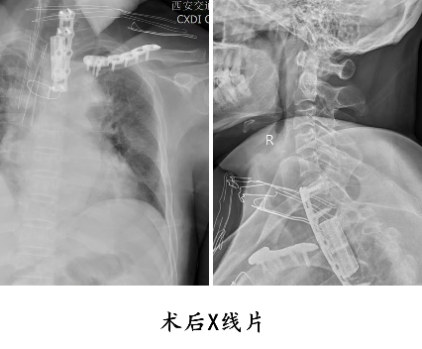

手术当日,麻醉团队蔡英敏教授、杨毅猛主治医师全程保驾护航,手术护理团队郭禹睿、张森渊完美配合,骨科中心王芳老师神经电生理精准监护,骨病与创伤科张纯教授和胸外科刘士源主任主刀、李永伟博士、乔文龙医师配合,采用左侧倒“L”切口,劈开胸骨及锁骨近端 1/3,撑开胸骨,成功突破解剖屏障,清晰暴露胸椎 1-3 椎体前方,精准实施胸椎 1、2 椎体次全切除,彻底解除脊髓压迫,并在骨缺损处植入3D打印融合器、辅以颈胸段前路钢板固定,重建脊柱稳定性。术后骨病与创伤科张格林、吴玮护理团队的精心护理下,患者右上肢及胸廓疼痛完全缓解,上肢肌力逐步恢复,且未出现开胸手术相关并发症,标志着这场多学科联合攻坚取得圆满胜利。